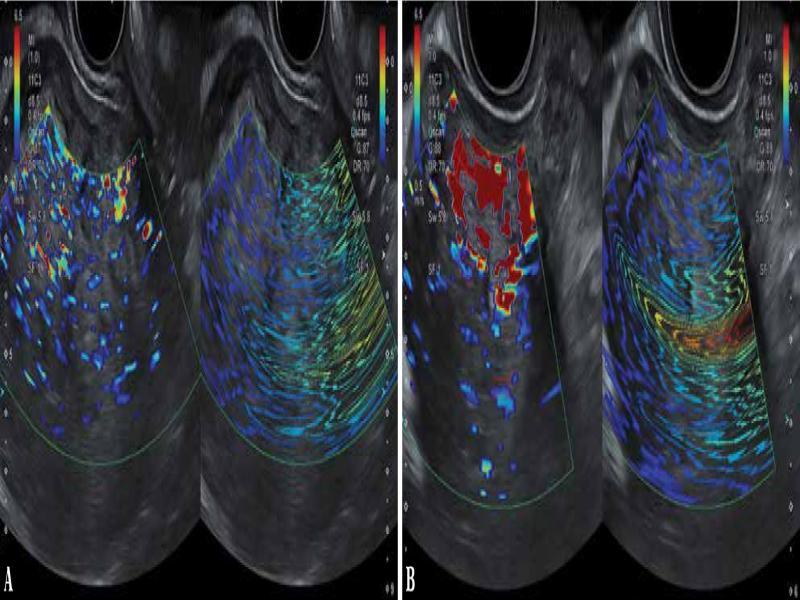

Fig. 1.